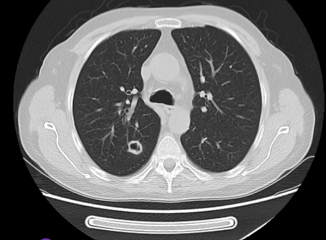

Anidulafungin ve gansiklovir tedavisinin altıncı gününde çekilen toraks tomografisinde kaviter lezyon saptanan hastada aşağıdaki etkenlerden hangisi veya hangileri akciğer enfeksiyonuna yol açmış olabilir?

Resim 1. Hastanın akciğer tomografisindeki kaviter lezyonu